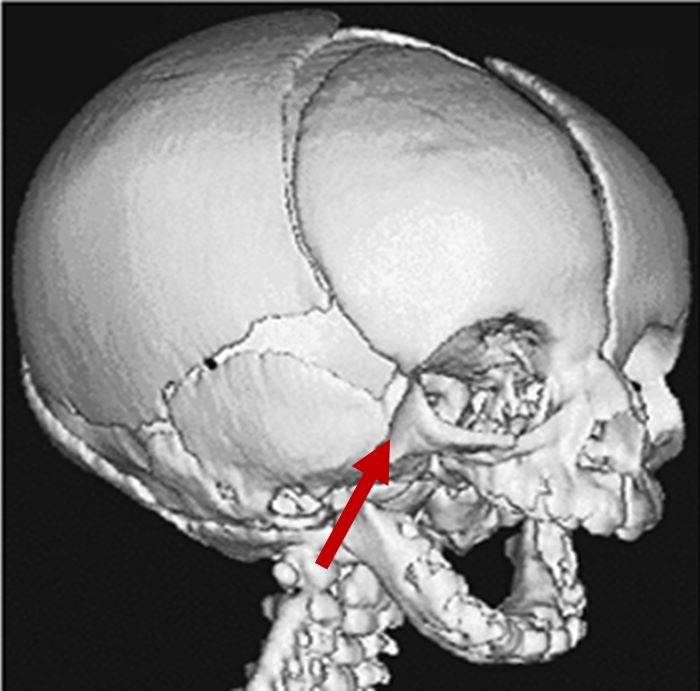

Mandibular hypoplasia

3D CT scan showing underdeveloped ramus and mandible

Radiographical features source 8